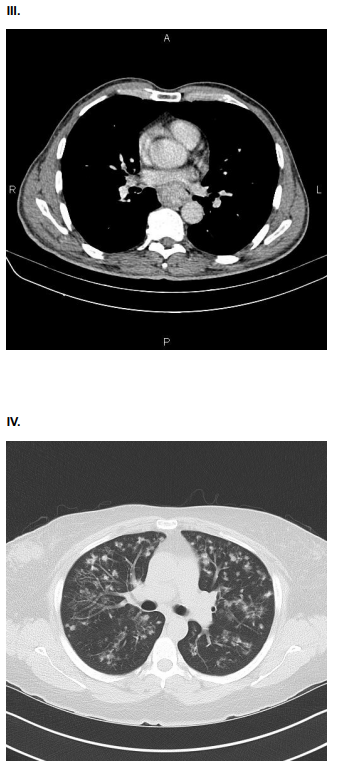

AMV, 75 anos, tabagista, com queixa de dor torácica súbito, do tipo lancinante. Ao exame físico: Regular estado geral. ACV: RCR em 2T, pulsos radiais assimétricos. PA: 150x80 mmHg. FC 110. Sat O2 90%. Solicitado ECG e Tomografia de Tórax e Abdome com contraste.

Assinale a alternativa que contenha o achado compatível com o quadro clínico da paciente.